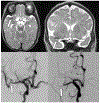

Results: Sixty-eight children met Duke criteria for infective endocarditis (43 definite and 25 possible). Twenty-three (34%) had identified neurologic complications, including intracranial haemorrhage (25%, 17/68) and ischaemic stroke (25%, 17/68). Neurologic symptoms began a median of 4.5 days after infective endocarditis symptom onset (interquartile range 1, 25 days), though five children were asymptomatic and diagnosed on screening neuroimaging only. Overall, only 56% (38/68) underwent neuroimaging during acute hospitalisation, so additional asymptomatic neurologic complications may have been missed. Children with identified neurologic complications compared to those without were older (48 versus 22% ≥ 13 years old, p = 0.031), more often had definite rather than possible infective endocarditis (96 versus 47%, p < 0.001), mobile vegetations >10mm (30 versus 11%, p = 0.048), and vegetations with the potential for systemic embolisation (65 versus 29%, p = 0.004). Six children died (9%), all of whom had neurologic complications.

Conclusions: Neurologic complications of infective endocarditis were common (34%) and associated with mortality. The true frequency of neurologic complications was likely higher because asymptomatic cases may have been missed without screening neuroimaging. Moving forward, we advocate that all children with infective endocarditis have neurologic consultation, examination, and screening neuroimaging. Additional prospective studies are needed to determine whether early identification of neurologic abnormalities may direct management and ultimately reduce neurologic morbidity and overall mortality.

Keywords: CHD; Infective endocarditis; infectious intracranial aneurysm; intracranial haemorrhage; neuroimaging; stroke.